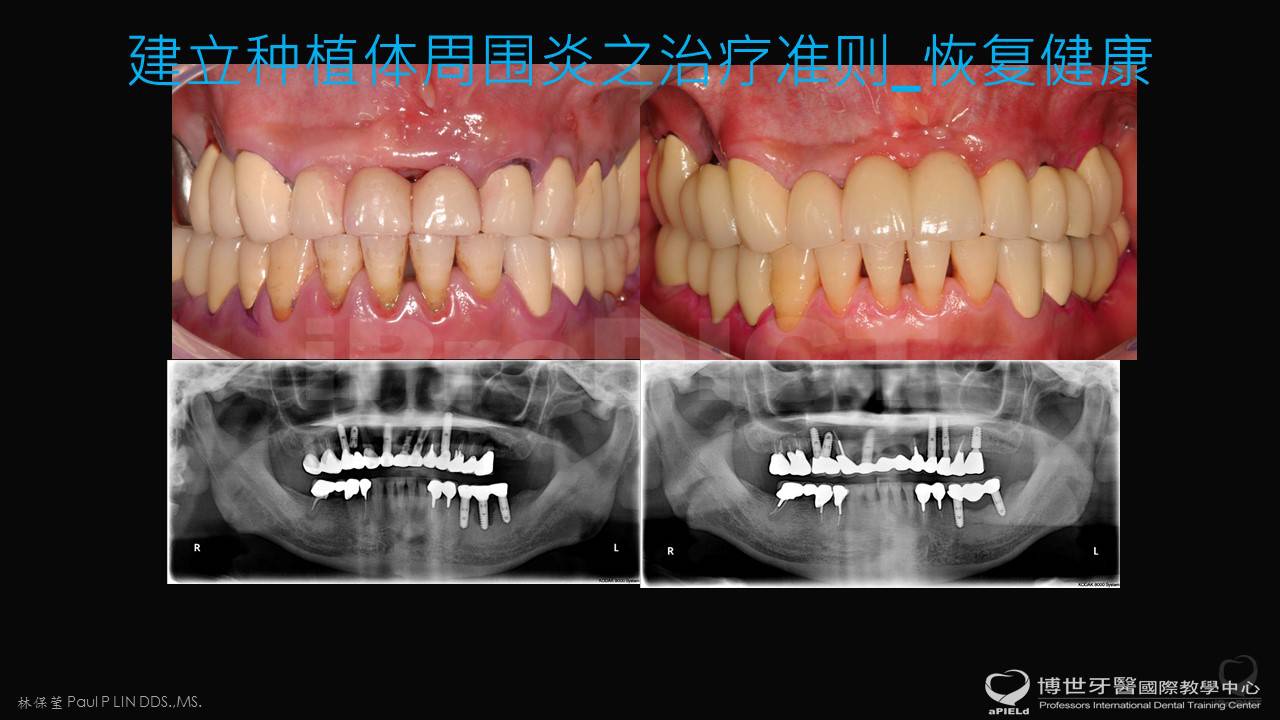

BIC_种植体周围炎之治疗

第二大主题

美观区BIC_缺陷之处置

第三大主题

美观区BIC_有疾病缺陷之处置